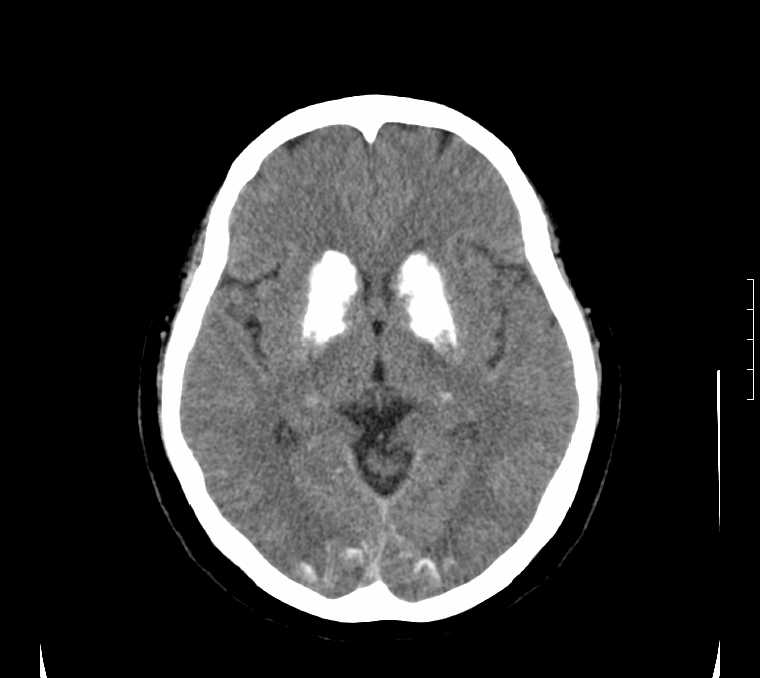

标题: CT24387:看看这例脑部改变!!

老年女性。头晕。

考虑:甲旁减。

fahr病

考虑甲旁低所致钙化。

鉴别于特发性家族性脑血管亚铁钙沉着症(fahr`s病)与甲状旁腺机能低下之间,请结合临床及相关实验室检查。